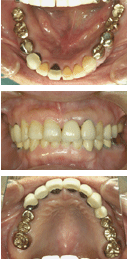

インプラントで治療する場合の適正料金の決め方として、従来のブリッジで治療する場合とほとんど同じくらいの価値を持っている(本当は両隣の歯を削らずに済むという遙かに高い価値があるのだが)ということで料金を決めることは一つの方法であると思う。

そこで、上顎中切歯が欠損し、欠損部にインプラントを植立してメタルボンド冠を装着する料金の算定として、両隣の歯を支台歯としてメタルボンドブリッジにする料金と同じくらいの料金設定にしてみることにする。

すなわち、メタルボンド冠が7~8万円として、ブリッジの場合全体で21~24万円ということになる。

それをインプラントとメタルボンド単冠で治療すると、インプラント植立料金として14~16万円となる。

これは1ピースAQBインプラントなら十分採算が取れるが、2ピースならかなり厳しいのではないかと思う。